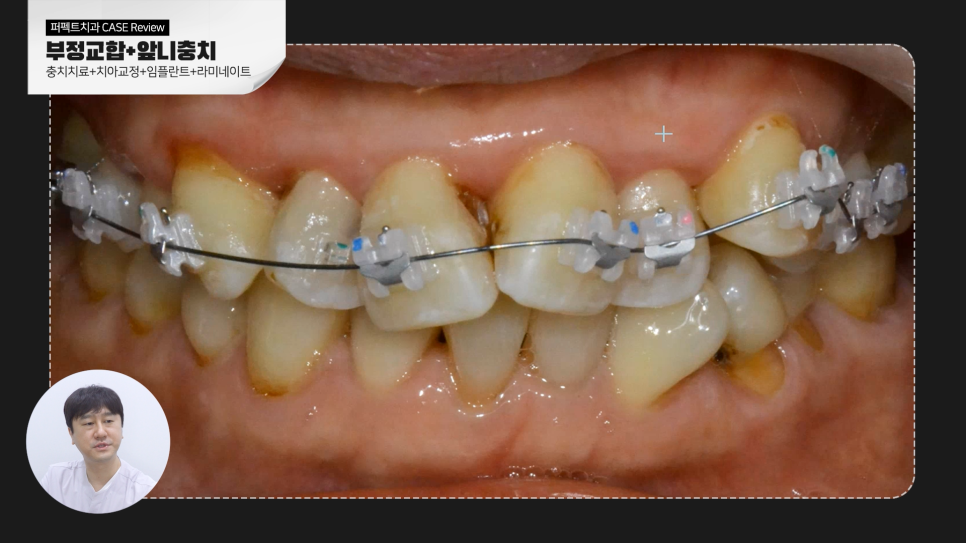

부정교합 + 앞니 충치 + 치아상실

이번 케이스는 복합적인 문제를 가지고 있습니다.

치료 전 정면 치아 상태만 봐도 상태가 좋지 않다는 것을 확인할 수 있습니다.

자세히 들여다보니 치아 배열과 교합이 맞지 않은 부정교합을 가지고 있었고

그러다 보니 치아 사이에 충치도 많이 보이고 있네요. 잇몸 상태도 안 좋았습니다.

심지어 어금니 부위는 치아를 상실한 상태기에 복합적인 문제를 해결하기 위해서는

한 가지 치료가 아닌 충치치료, 교정치료, 보철치료, 임플란트까지

치과에서 할 수 있는 다양한 치료가 동반되어야 했습니다.

충치가 더 진행되기 전에 충치치료를 먼저 진행하고 부정교합을 개선하기 위해 전체교정을 진행했습니다. 클리피씨(clippy-ceramic) 장치를 사용해 교정을 진행하였는데 치아의 이동이 원활해 교정 기간은 약 10개월 정도 소요되었습니다. 교정으로 치아 배열이 가지런하게 된 덕분에 앞니 충치를 제거 후 자연 치아를 많이 손대지 않고도 심미보철 '라미네이트'를 통해 치료와 동시에 심미적으로 개선할 수 있었습니다.